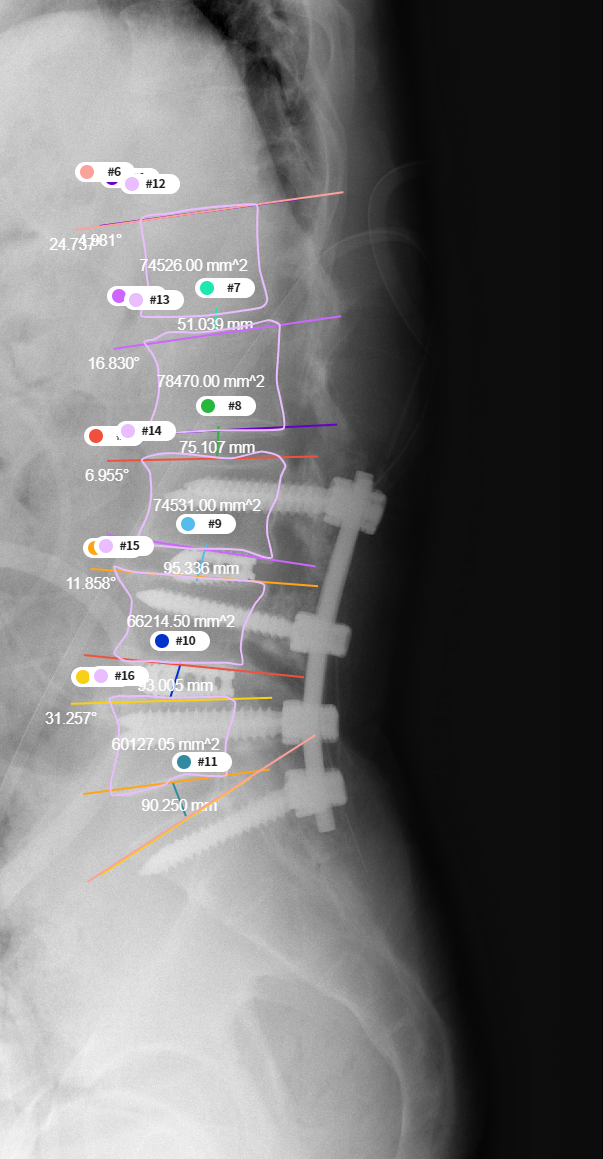

– Dice Coefficient Score 등데이터 비율 23776장 5944장 746장 - Predict 결과물의 각도와 거리 측정

- Predict mask 이미지의 외곽선을 추출하는 contour 기능을 이용하여 4번 5번 요추를 검출하고, 해당 데이터의 각도와 거리 측정

- 측정된 각도와 거리를 실제 측정값과 비교하여 Pearson-Correlation 분석

[요추 4, 5번 간의 디스크 높이 및 각도 측정]